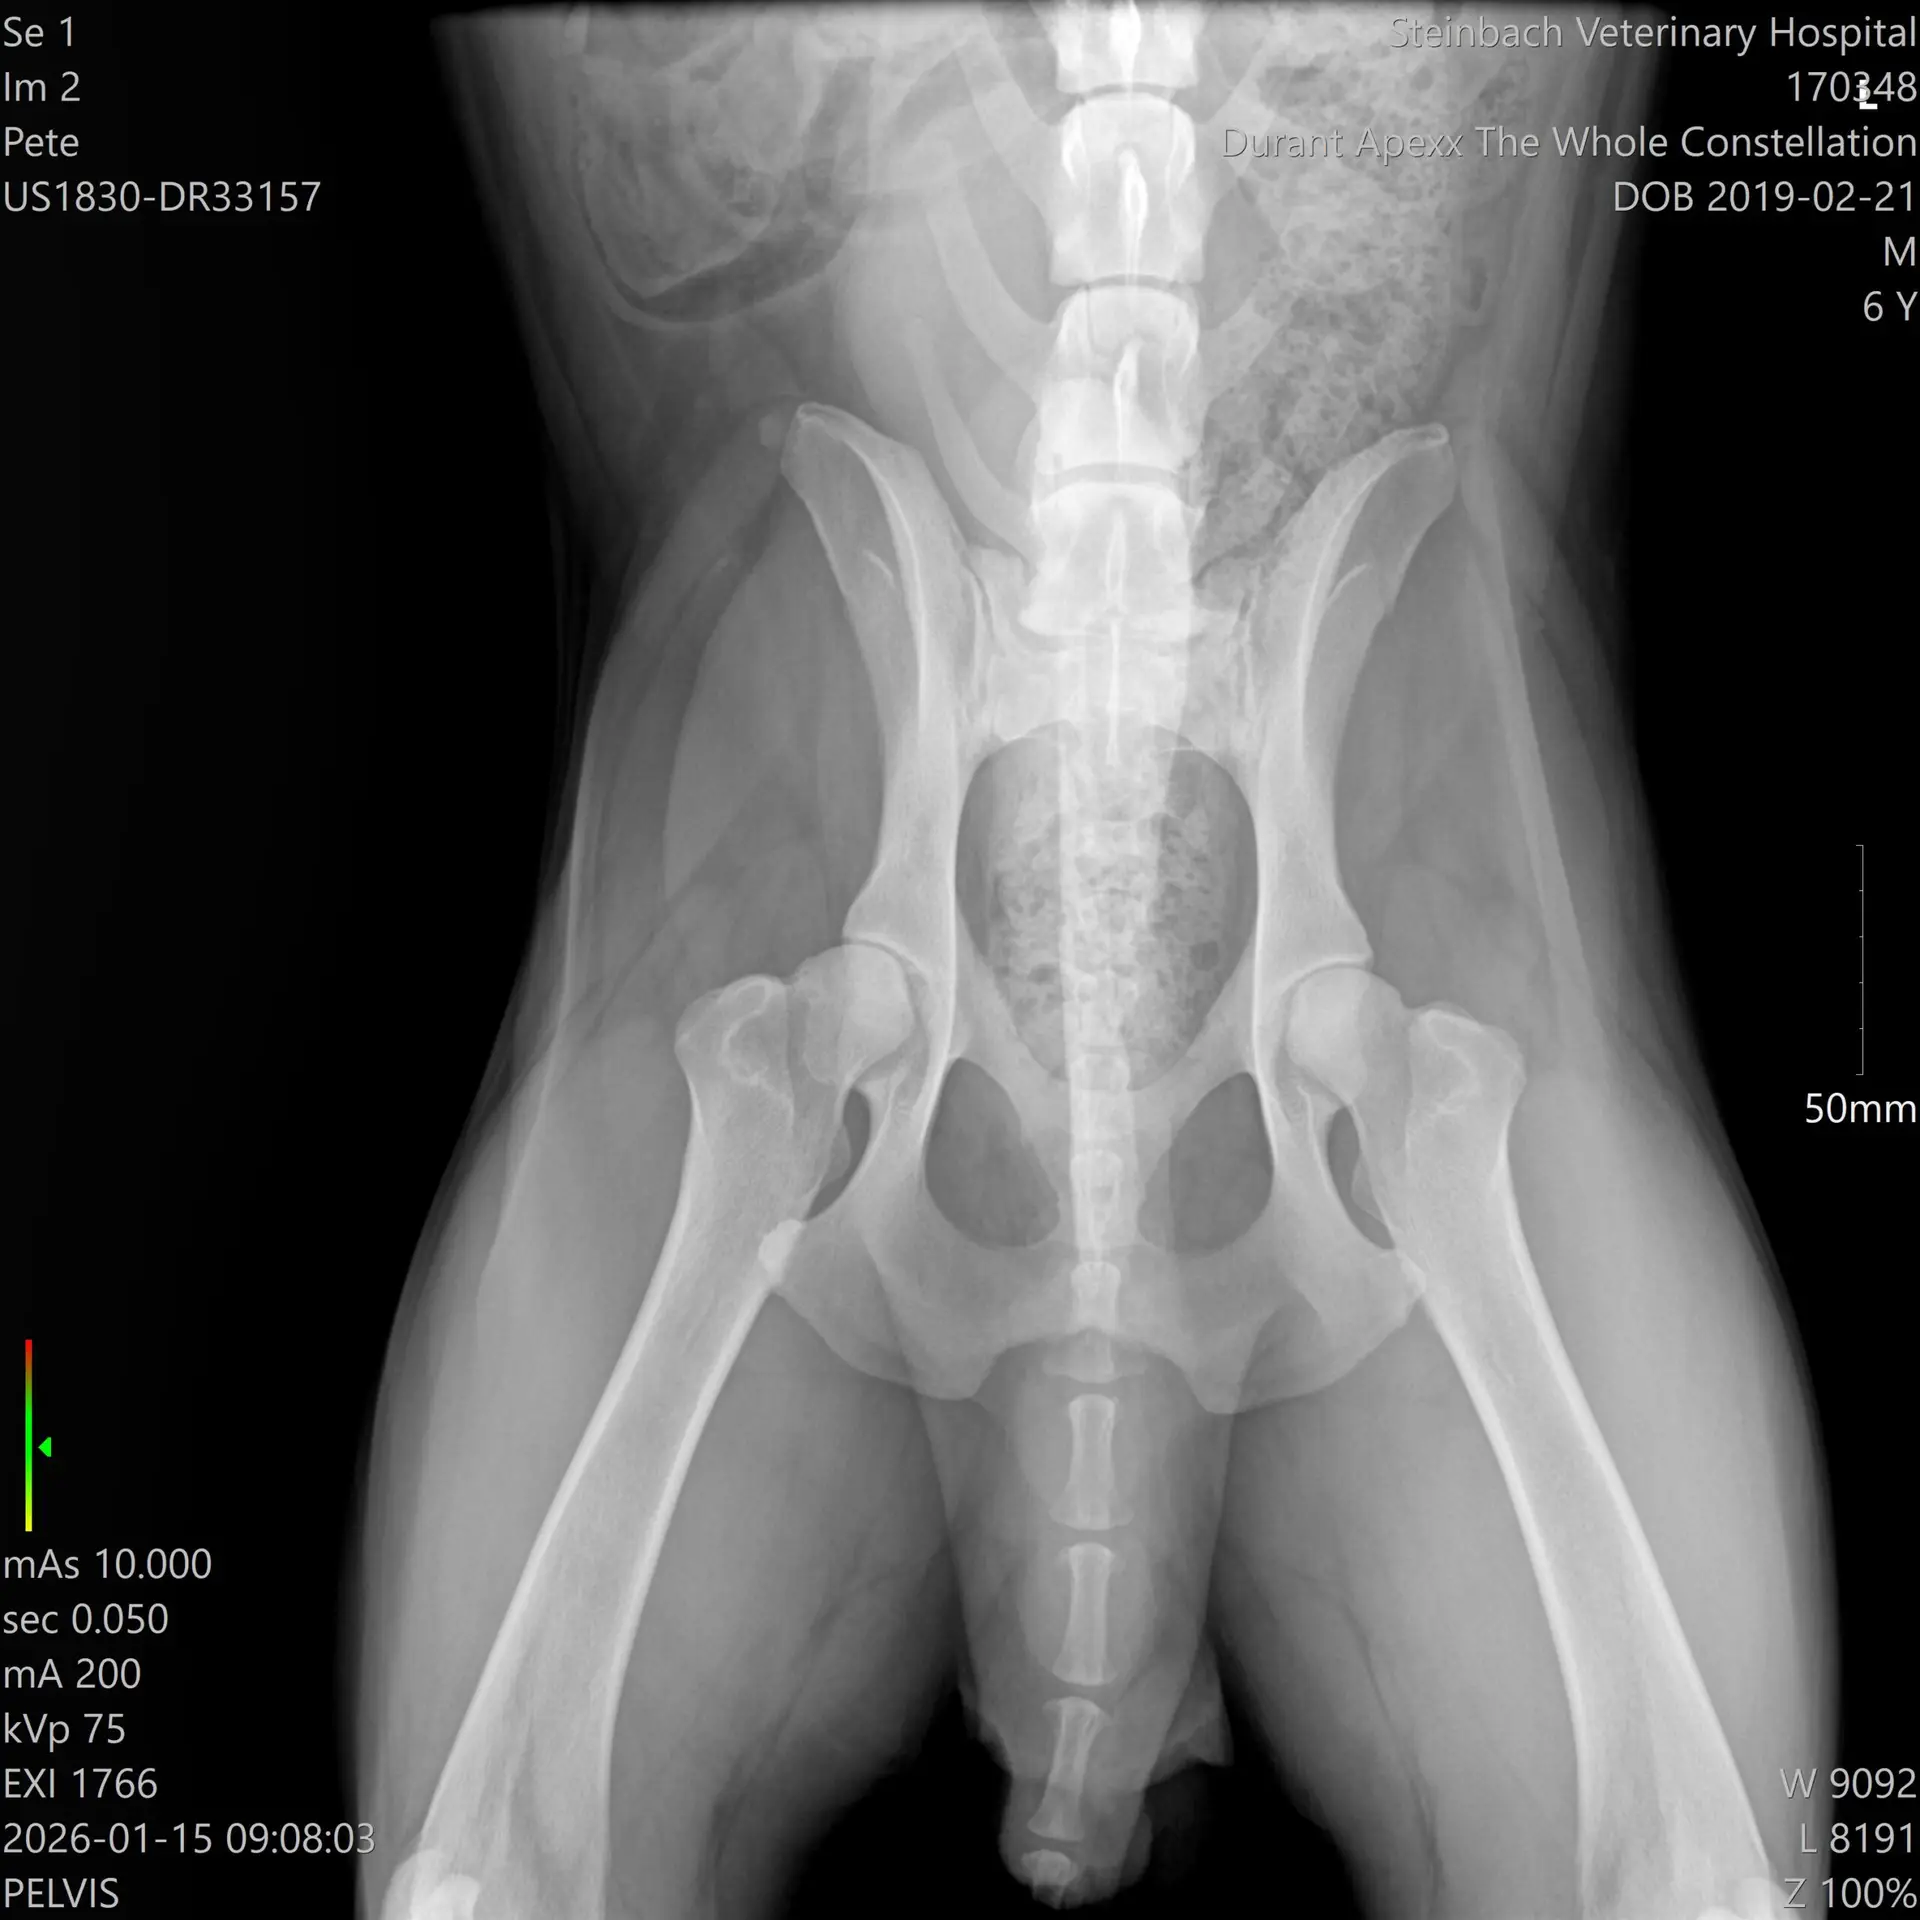

What OFA clearances actually mean, how to read the ratings, how to verify results on ofa.org, and the red flags that should end any breeder conversation. Includes Ash's actual January 2026 radiograph from Steinbach Veterinary Hospital.